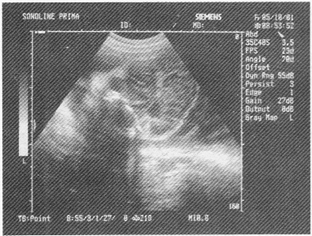

1.女性,28歲,停經27周,產前超聲檢查如圖,最可能的診斷為

A.胎兒畸形,腦積水

B.胎兒畸形,臍膨出

C.胎兒畸形,多囊腎

D.胎兒畸形,無腦兒

E.胎兒畸形,露腦畸形

正確答案:D解題思路:顱骨強回聲光環消失,眼球突出呈蛙樣面容且羊水過多。